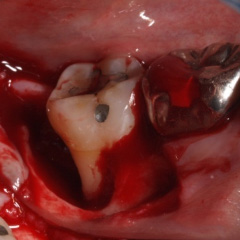

| 歯周病が進行したケースでは盲目下でポケット内の歯石を確実に除去するには限界があります。 | 局所麻酔をした後、歯茎を切開し、明視下にて歯根面の歯石や炎症組織を取り除き、歯周ポケットの除去をおこないました。 |

| 深い虫歯のケースでは、切除療法を行い虫歯を取り除き、健全な歯質を歯肉の上に出し、歯肉の盛り上がりを数ヶ月待ってから歯型をとります。 |